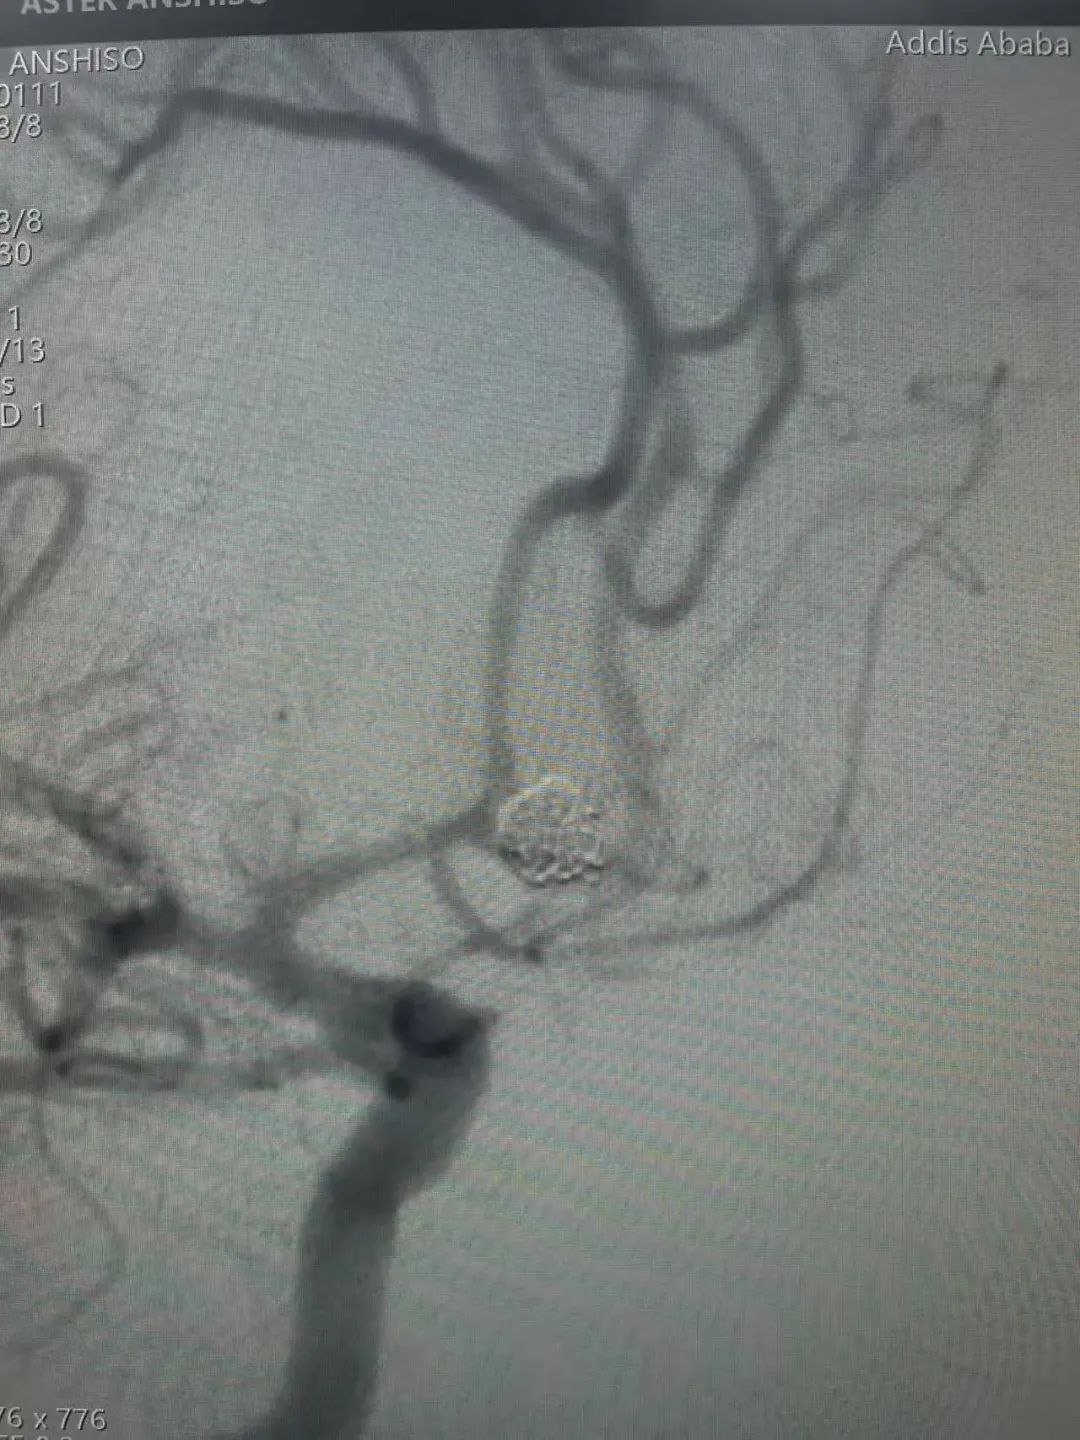

术前影像

术后影像

使用弹簧圈尺寸

Jasper®颅内可电解脱弹簧圈5*15、4*8、3*8、2*6、1.5*3各一枚